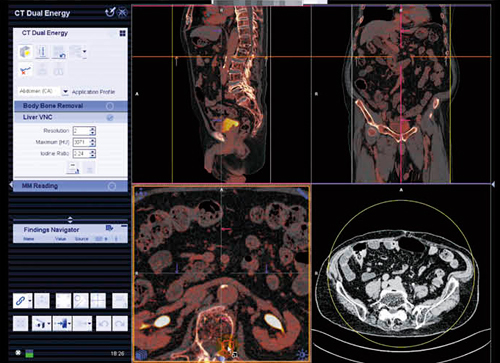

●Dual Energy

syngo.viaのDual Energyは,Two-material decompositionやThree-material decompositionの解析を,ワークステーションではなく読影端末上で行えることが特長である。図8は,腎結石に対するTwo-material decomposition解析であるが,石灰化結石を青く表示させている。また,Three-material decomposition解析のLiver VNC(Virtual Non-Contrast)では,仮想的非造影画像の作成や,Iodine mapの作成などが可能である(図9)。これらの処理が,ワークステーションではなく読影端末で可能になったことが大きなメリットである。

図9 syngo Dual Energy

Liver VNC解析